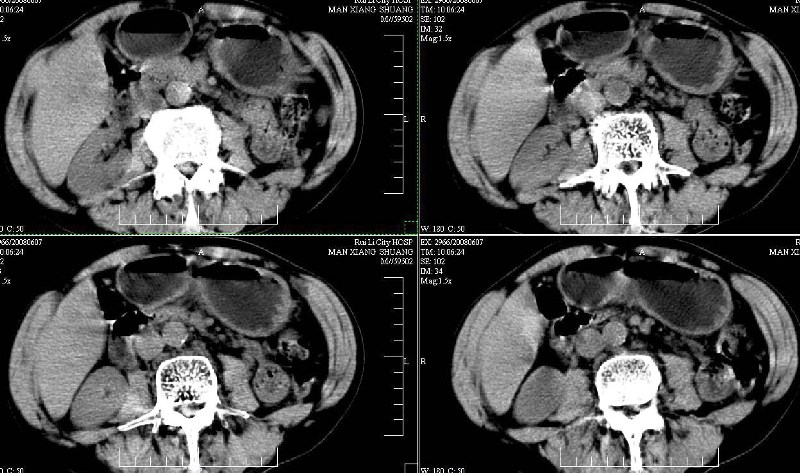

标题: CT13937:M,42A.腰疼一周。 [打印本页]

标题: CT13937:M,42A.腰疼一周。

ct(椎间盘扫描):椎间盘炎,建议dr。

dr:l4骨质破坏,转移可能。

胸部摄片未见异常。临床医生体检发现上腹部饱满。

ct:肝癌腰椎转移。临床医生:肝脏、骨转移,肿瘤来自?前列腺?!